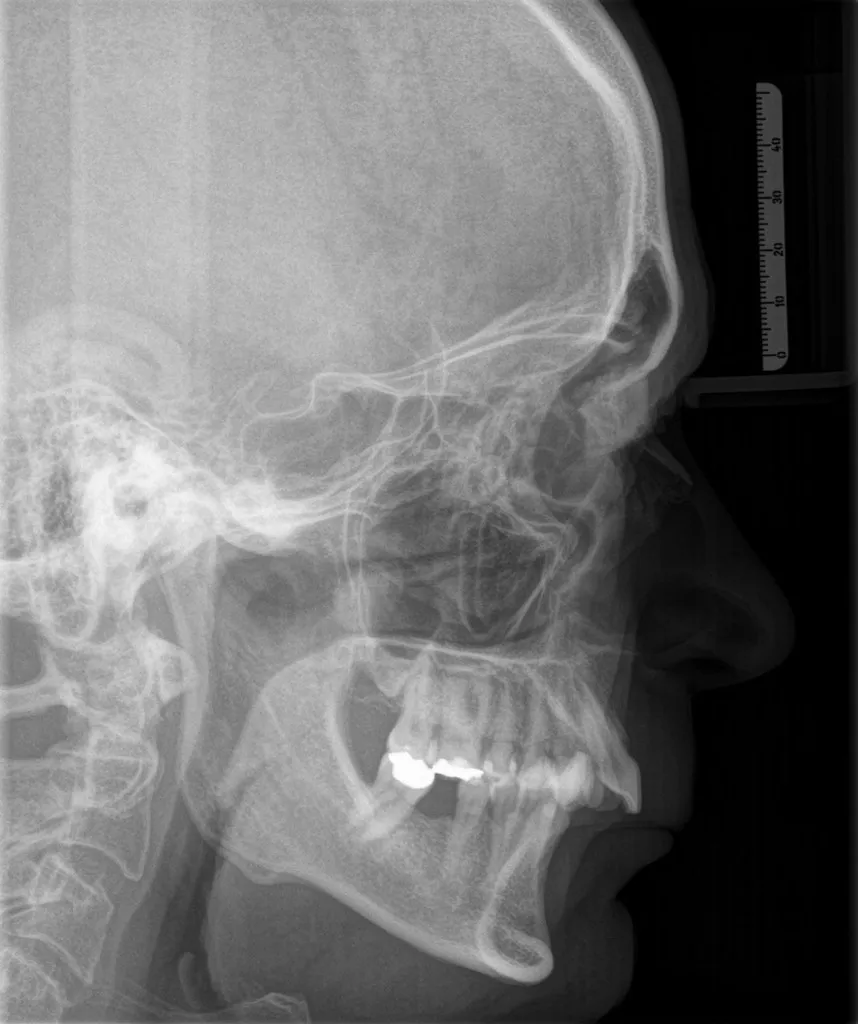

In unserer Praxis ist die kombinierte kieferorthopädisch-kieferchirurgische Behandlung ein zentraler Schwerpunkt. Diese Therapieform eignet sich besonders bei ausgeprägten Kiefer- und Zahnfehlstellungen (Dysgnathien), die nicht nur die Gesichtsästhetik beeinträchtigen, sondern auch funktionelle Einschränkungen wie Probleme beim Kauen, Sprechen oder Atmen verursachen können.

Wenn Ober- und Unterkiefer unterschiedlich stark entwickelt sind, kann nach abgeschlossenem Wachstum eine kombinierte kieferorthopädisch-kieferchirurgische Behandlung notwendig werden. Dabei wird die Position eines oder beider Kiefer chirurgisch korrigiert, um Funktion und Ästhetik nachhaltig zu verbessern.

Für die kieferorthopädische Vor- und Nachbehandlung verwenden wir festsitzende Zahnspangen, die während und nach der Operation getragen werden müssen.